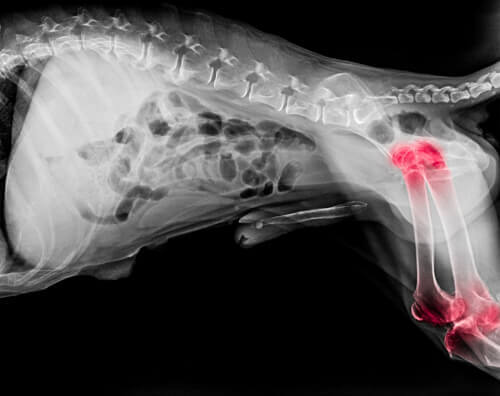

En flott helsefordel med spirulina for hunder er grunnet fykocyaninet, et betennelsesdempende stoff som reduserer smerter. Dette er spesielt hjelpsomt når en hund har en skade eller nylig har blitt operert.

Disse algene er også en naturlig behandling mot leddgikt og forbedrer din hunds daglige rutine i stor grad. De har heller ikke ulempene med syntetiske betennelsesdempende midler, som å skade leveren.